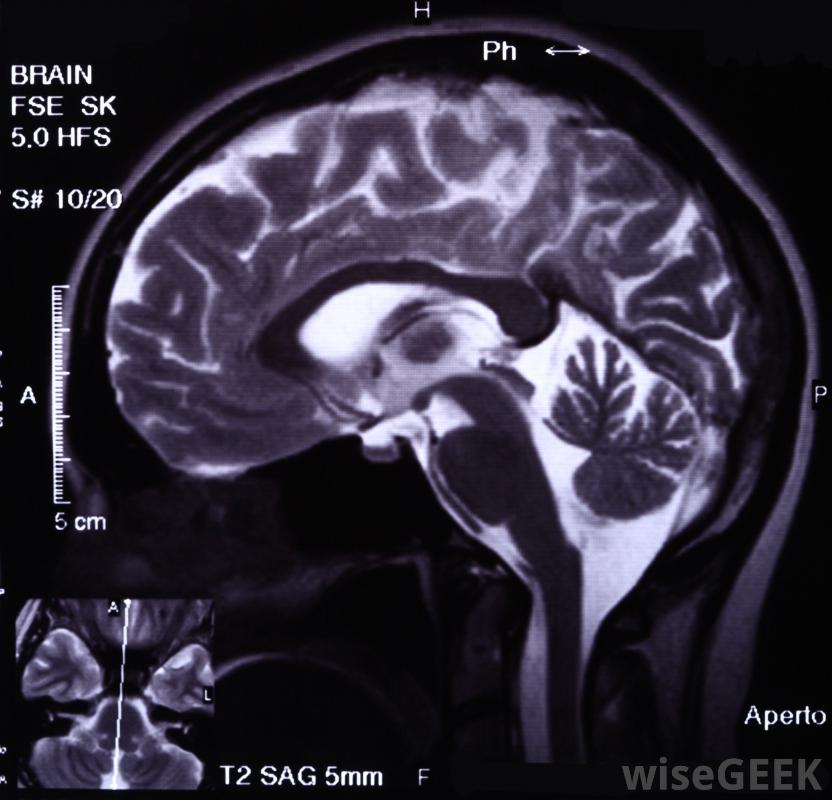

癫痫是一种慢性神经系统疾病,由于大脑中神经元活动异常,会影响大脑中负责记忆的区域。当癫痫发作发生时,与记录记忆的大脑区域相连的神经递质就会中断。之后,短时记忆丧失癫痫发作是很常见的-患者可能不记得他们在哪里或他们在做什么;有时,完全健忘症可能会持续长达一个小时。最终,反复发作的癫痫会对大脑的记忆区域造成损害,并导致永久性的记忆丧失。癫痫对记忆的影响会影响这两个区域癫痫对记忆的长期影响也会导致语言和语言的困难。癫痫对记忆的长期影响也会导致语言和语言的困难。癫痫对记忆的影响有很好的记录,那些患有这种疾病的人比那些患有其他神经系统疾病的人更容易出现记忆丧失问题。

严重的脑损伤可能是癫痫发作的原因和后果。大脑记录记忆通过一种被称为编码的过程,信息被分为两类,短时记忆(STM)只会回忆几分钟的信息,长时记忆(long-term memory,LTM)能长时间储存信息,大脑需要不断的监测才能使记忆正常工作,癫痫发作的发生会导致这一过程的中断

大脑癫痫可能是由于长期服用药物引起的长期来看,癫痫发作会对大脑造成永久性损害。癫痫通常会影响大脑的特定区域,反复发作通常会对脑组织造成损害,由于癫痫患者大脑中持续的异常电活动,癫痫发作之间也会发生损伤。

某些类型的癫痫发作可能会导致持续性发作脑损伤由于大脑的不同区域受到伤害,可能会出现不同类型的记忆丧失。一个右侧大脑受到影响的人可能会出现视觉记忆问题,而左侧大脑受损会影响言语记忆,从而导致书写和言语受限。癫痫袭击额叶通常会导致无法集中注意力。癫痫的治疗方法还不清楚,有几种治疗方法可以限制癫痫对记忆的影响。医生通常会开抗惊厥药来控制或完全消除癫痫发作,从而保留大脑功能和记忆。在极端情况下,当药物对阻止癫痫发作复发作用不大时,可能需要动手术患有癫痫对记忆有影响的人通常也会寻求记忆训练。一般来说,记忆改善是不可能的,但是使用记忆法和其他记忆辅助手段的训练可以改善日常生活。训练必须是单独设计和专门的,以治疗癫痫对记忆的特殊影响。